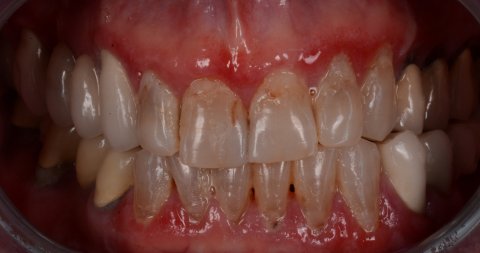

Smile makeover is an umbrella term used for dental treatments improving the appearance of the smile. Such a hollistic approach may consist of cosmetic dentistry procedures, such as dental veneers, composite bonding, tooth implants and teeth whitening.

A Smile Makeover uses one or more dental procedures to enhance the appearance of your smile. A Smile Makeover will factor in numerous aspects of your appearance, including skin tone, hair colour and lip shape, along with the shade, shape and condition of your teeth, to create and perfect your ideal smile.

A complete overhaul of your smile may involve a number of techniques, depending on your individual circumstances and treatment objectives.

No two smiles are the same, and neither are two Smile Makeovers. However, some of the more common problems addressed by a Smile Makeover include:

Tooth Colour

Existing silver or amalgam restorations (filings, crowns, etc) can be replaced with composite, zirconium or porcelain alternatives that perfectly match the natural colour of your teeth.

Professional tooth whitening can be used to improve the appearance of mild to moderately discolored or dull looking teeth. At our clinic, we use the Opalescence system, a market leader in teeth whitening for 25 years, for inner teeth and the Beyond system for the tooth surface. If teeth are too severely stained to be improved by tooth whitening, veneers may be recommended instead.

In the case of crooked, overlapping or gappy teeth, veneers can be used with great success. If necessary, orthodontics may also be used to straighten and correct problematic areas.

General Harmony

If the balance of your smile is suffering as a result of uneven, chipped or cracked teeth, composite bonding may be the ideal solution. In other cases, a more harmonious effect can be achieved by re-contouring the teeth with enamel Microabrasion. With both methods, a minimal amount of work can result in a major difference to your smile.